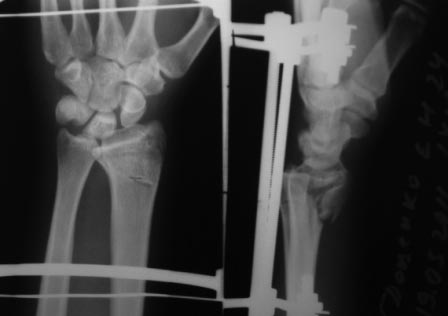

• Re: перелом луча

Отправитель: Victor 16 Октябрь 2011, 14:16

Нет не в вывихе, т. К. Из-за спицы проведенной через обе кости предплечья, то ротационные движения и подвижность локтевой кости резко ограничены, это может в некоторых проекциях расцениваться как подвывих, если найду покажу финальный снимок, там все рентгенологические показатели восстановлены.

Отправитель: Victor 17 Октябрь 2011, 14:05

АВФ очень разнообразны, мы (отделеие хирургии кисти ГКБ 4 г. Москвы) используем только две полудуги и две штанги смонтированные на двух спицах Киршнера, проведенных через кости предплечья и основания 2-5 пясьных костей (аппарат Лазарева-Коршунова), дополнительных спиц не проводим.